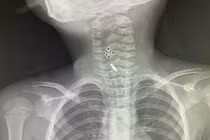

Người bệnh là bà N.T.H (57 tuổi, trú tại Hà Nội) nhập viện trong tình trạng khó thở, tức ngực sau khi nuốt phải hạt kha tử kích thước khoảng 1cm. Kết quả chụp CT cho thấy dị vật nằm tại phế quản gốc phải, sát vị trí phân nhánh phức tạp, gây bít tắc hoàn toàn đường thở.

Ê-kíp của bác sĩ CKI Phạm Thị Út Trang – Phó Trưởng Khoa Nội hô hấp đã phối hợp với bác sĩ gây mê hồi sức đã nhanh chóng tiến hành nội soi phế quản ống mềm, phát hiện dị vật góc cạnh khoảng 1cm là hạt kha tử hình bầu dục, bề mặt trơn nhẵn, hai đầu nhọn nằm chắn, gây bít tắc trong lòng phế quản gốc phải, ngay sát vị trí chia nhánh phế quản phân thùy - khu vực giải phẫu hẹp, góc rẽ nhánh phức tạp khiến việc gắp dị vật gặp khó khăn. Ê-kíp nội soi can thiệp đã khéo léo tiếp cận và thành công gắp dị vật ra khỏi lòng phế quản bệnh nhân. Sau can thiệp, sức khỏe của bệnh nhân ổn định, thở dễ dàng, không còn cảm giác tức ngực, được xuất viện sau 24h theo dõi.